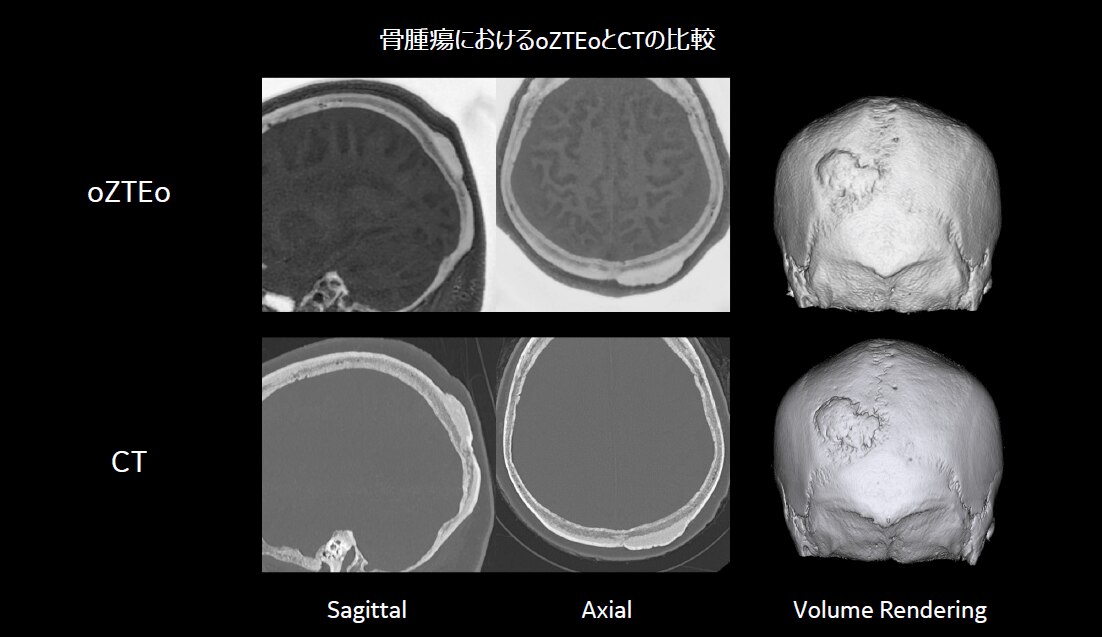

◆ Case2. 骨腫瘍(osteoma)

病変部位の形状変化を経過観察する必要があるが、その後のフォローアップではMRIにて検査を実施している。長期間の経過観察を行っている患者については、MRIのみでのフォローアップへの切り替えが可能となると考えている。骨腫瘍においては、短期間にサイズが増大することで悪性腫瘍の可能性が出てくると言われており、徐々に大きくなる場合は良性の可能性も含まれる。そのため、腫瘍サイズの経時的な確認が重要となる症例である。

脳神経外科医からは、「これらCase1、2、3の症例は全てCTとMRIの両検査にて経過観察中であった症例であるが、oZTEoによって骨情報の取得が可能になったことで、病変の大きさ、形状変化に対しての診断はMRIのみで可能である。」とコメントをもらっている。症例によってはCTを省略し、MRIのみでの評価が可能であり、患者負担を軽減することが期待できる。